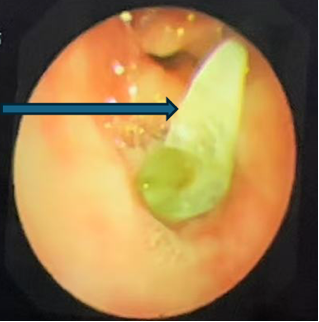

支气管镜下的景象触目惊心:乐乐右主支气管管腔内满是脓性分泌物,且增生的肉芽组织堵塞了右上叶支气管开口。在更深处,一个看似尖锐异物死死堵住了右中间支气管管腔。

支气管镜检查显示右中间段支气管异物堵塞,镜下看似尖锐,表面大量黄绿色分泌物附着

在呼吸科支气管镜室,张东伟主治医师和叶颖龙主管护师紧密配合,小心清理了分泌物,最终用异物钳成功钳取出异物——竟是一颗草莓味糖果的包装纸!展开测量,长度接近3.5厘米。